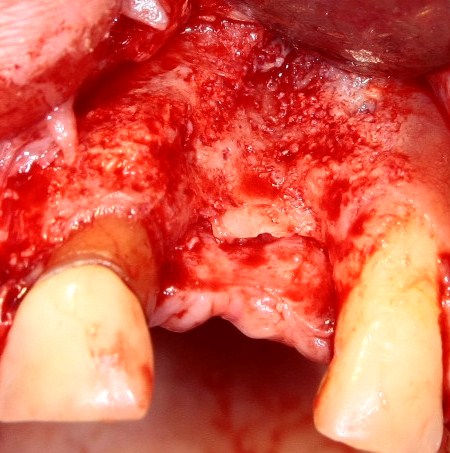

Делаем разрез в пределах кератинизированной десны. Скелетируем кость, видим следующее:

По краям от лунки видны остатки прошлых операций. Это не кость, а грануляции вперемежку с твердыми частичками биоматерила. Жди мы хоть несколько лет — вряд ли они организовались в приемлемую для имплантации костную ткань. Поэтому мы всё вычищаем, до естественной кости:

Ее объем, как мы видим, небольшой, использовать его для ПРАВИЛЬНОЙ установки импланта нереально. Почему выделил слово «ПРАВИЛЬНОЙ»? Потому что некоторые типы имплантационных систем позволяют установить имплантат хоть куда, хоть в какой объем кости, если очень хочется, конечно. Но ведь у нас нет задачи «воткнуть» имплантат всеми правдами и неправдами, верно? Комплексная цель лечения — воссоздание полноценно функционального зуба со всеми окружающими тканями. Чем мы, собственно, и занимаемся.